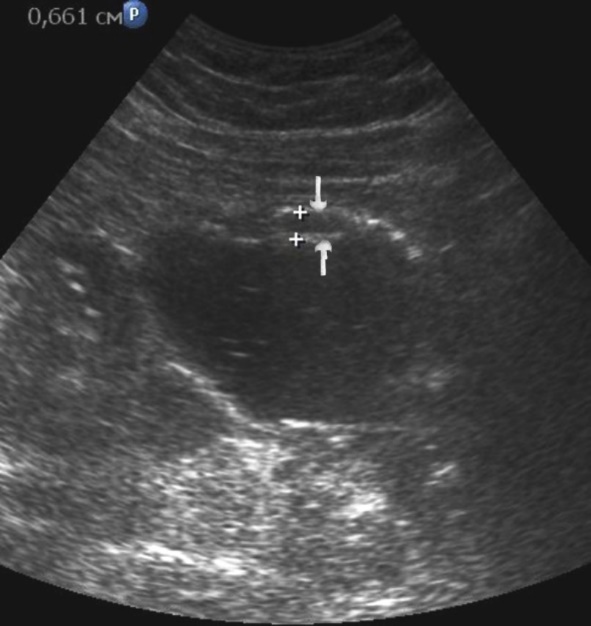

Distal gastric cancer was observed in 24 (39,3%) cases and contributed to the development of pyloric stenosis: in 6 (9,8%) cases it was compensated, in 18 (29,5%) – was sub compensated. The layers of the wall were not differentiated in all patients with sub compensated pyloric stenosis. In the case of compensated pyloric stenosis, the thickness of the affected area was 10,2±2,9mm, the length was 27,1±6,2mm, the diameter of the pylorus was 8,3±0,8mm (Figure 14). Among patients with sub compensated pyloric stenosis, the thickness of the stomach wall was 19,8±4,1mm, the length was 43,6±4,5mm, the pyloric diameter was 4,3±1,1mm (Figure 15).

Figure 14.Gastric carcinomas of diffuse infiltrative form in the atrium of T2 stage. Compensated pyloric stenos. On an empty stomach in the cavity of the stomach is determined an a small amount of fluid. The diameter of the pyloric canal more than 7 mm.

Figure 15.Distal gastric carcinomas of diffuse infiltrative form of T3 stage. Sub compensated pyloric stenos (arrows). The thickness of the anterior wall of the stomach is 9,13 mm, extent of the affected area – 7,84 cm. On an empty stomach in the cavity of the stomach is determined an a large amount of fluid. The diameter of the pyloric canal is about 6 mm.